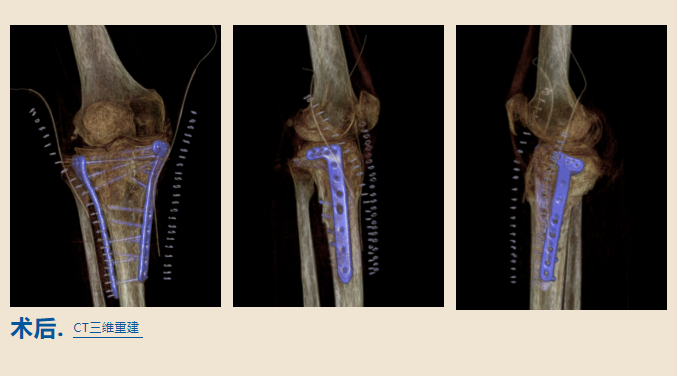

手术需要将畸形愈合的骨头

重新断开

恢复力线和关节面平整

这样

王大姐就能重新走路了

由查晔军院长

和北京积水潭医院郑州医院

创伤骨科主任刘国会联合手术

手术进行了整整两个小时

专家们非常仔细地操作着每一个步骤

当手术结束后

医生告诉王大姐

非常成功

她的腿将会逐渐恢复到正常状态